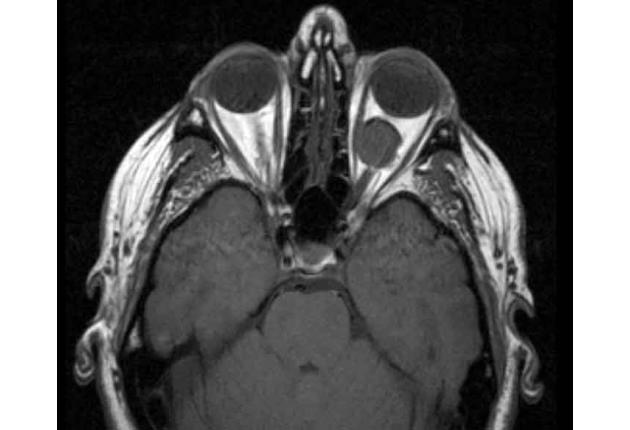

July 15, 2020Intro to Orbital & Intraocular Tumors

Dive into the many manifestations of ocular tumors through diagnosis based on patient history and examination, and diagnostic imaging. Over the course of an …